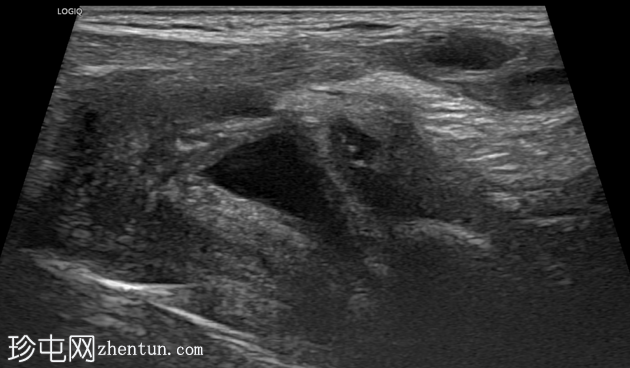

右侧努克氏疝管长约6毫米,内含部分子宫和卵巢(大小约1.5 x 1厘米)。在整个检查过程中,这些组织均保持原位。

对侧附件呈多囊性改变,大小约3 x 1.8厘米。

上述超声特征清晰地显示了努克氏疝管的内容物及其延伸范围;其中包含患者的一侧卵巢和部分子宫组织。

这些特征符合卵巢努克氏疝的诊断。